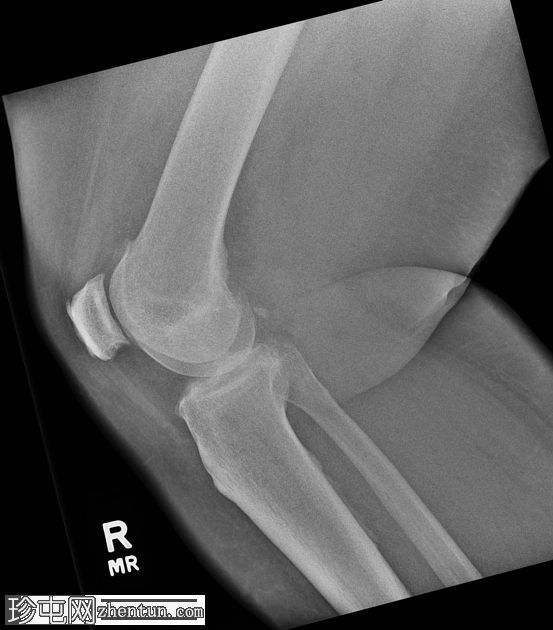

斜位片

右膝中度骨关节炎(3级),表现为内侧胫股关节和髌股关节间隙狭窄,边缘可见骨赘、髌骨骨刺和胫骨棘突。

内侧副韧带近端附着处股骨内侧髁附近可见长圆形软组织骨化,提示为佩莱格里尼-斯蒂达(Pellegrini-Stieda)损伤。